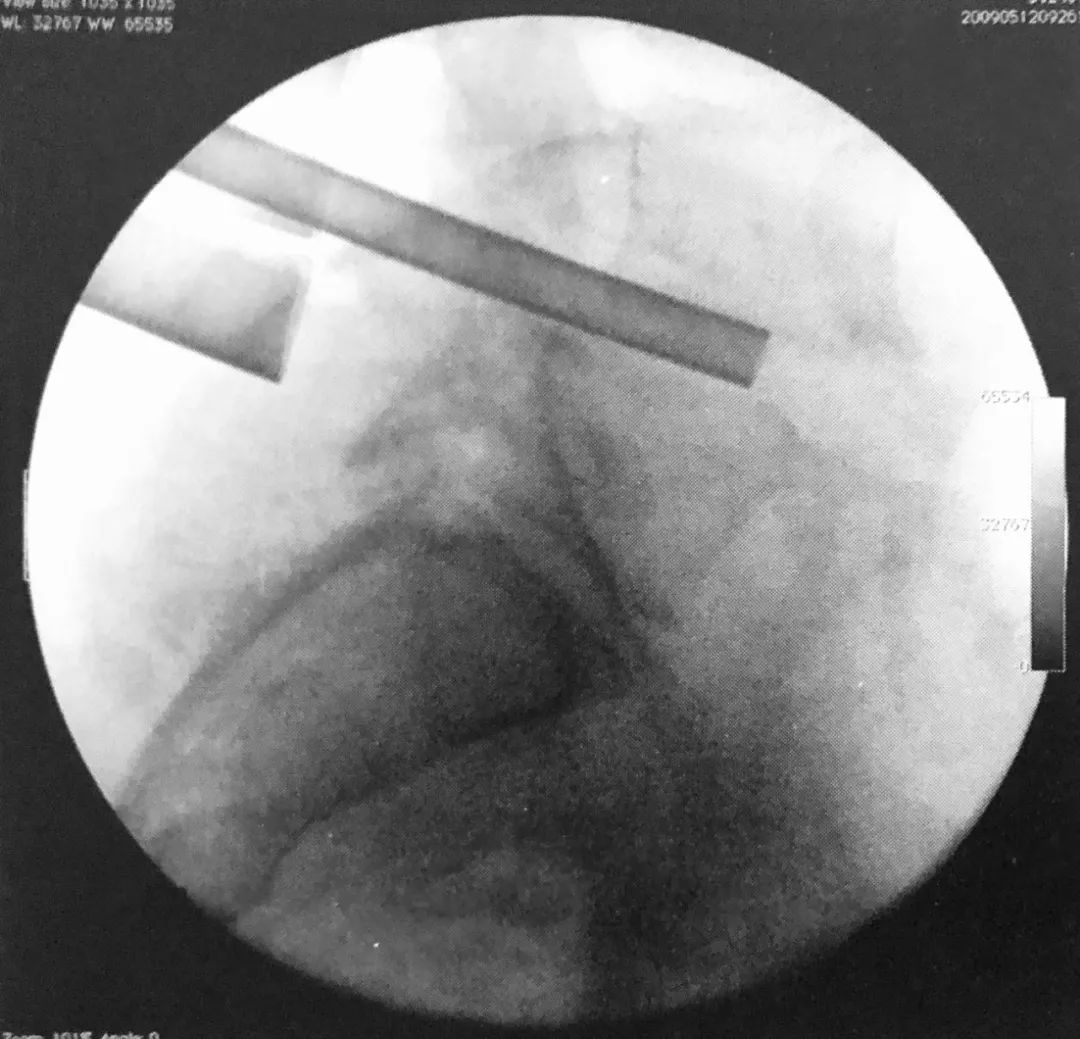

5. 术中透视证实球囊位于椎体前部,这可避免骨折块向后突入椎管。

7. 透视下向椎体内注入骨水泥,在正侧位片上仔细观察以确保椎体边缘不被侵犯。如果发现骨水泥溢出,则停止注入。应避免将骨水泥注入椎体后部。

8. 理想情况下,正位片上骨水泥充填应该通过中线。